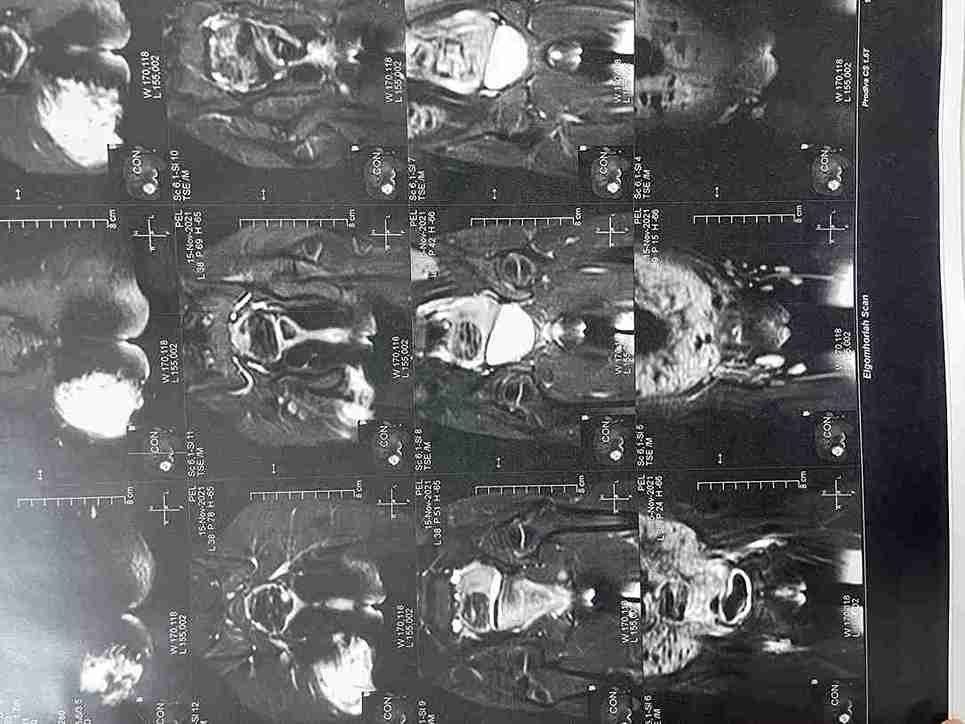

تم في هذه الحالة استئصال ورم حميد نادر (شوانوما) كان موجوداً على غلاف العصب الوركي (عرق النسا) الأيمن لطفلة تبلغ من العمر 5 سنوات ونصف. الورم كان يضغط على العصب مسبباً ألماً في منطقة الفخذ والأرداف. تمت الجراحة بنجاح تام مع الحفاظ الكامل على سلامة ووظيفة العصب.

• نتائج التحليل النسيجي أكدت أن الورم حميد (شوانوما).